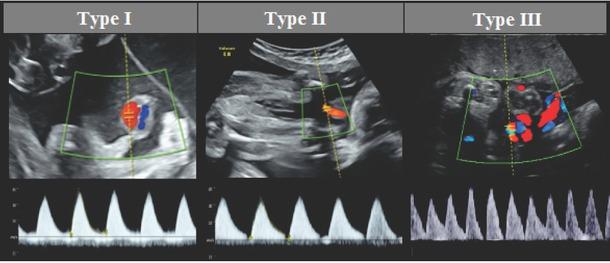

Figure S1